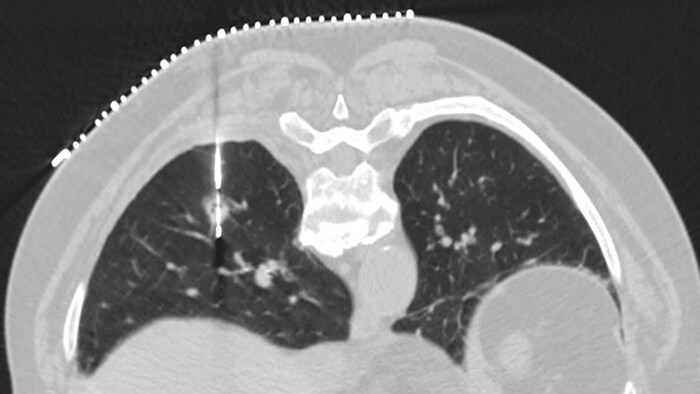

Enhance diagnostic confidence Simultaneously reduces dose and improves image quality to meet your clinical goals

Enhance diagnostic confidence Simultaneously reduces dose and improves image quality to meet your clinical goals

ContinueAl provides advances that allow for a low-dose image with greater diagnostic confidence

ContinueAl provides advances that allow for a low-dose image with greater diagnostic confidence

Experience the image quality that can be achieved with simultaneously up to 80% less dose, up to 85% less noise and up to 60% improved low-contrast detectability.3 Precise Image has a familiar image appearance that closely resembles filtered back projection (FBP). You’ll also see best-in-class low-contrast resolution.

Slide the bar to compare images without and with Precise Image.